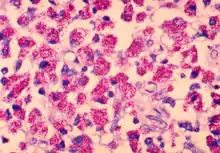

Mycobacterium avium is a species of the phylum Actinomycetota (Gram-positive bacteria with high guanine and cytosine content, one of the dominant phyla of all bacteria), belonging to the genus Mycobacterium.

Present mainly in cattle and humans with an immunocompromised disorder, e.g. AIDS, it is transmitted to man by drinking unpasteurized cow milk. Pigs are susceptible to M. avium avium , M. bovis, and M. tuberculosis, with M. avium being most common. Lesions are typically lymphoid, gastrointestinal, or rapidly progressive disseminated forms. Intradermal testing is the diagnostic test of choice. Isolation of purified protein derivatives is useful for M. bovis and M. tuberculosis. However, cross-reaction between M. avium avium, M. tuberculosis, or M. avium paratuberculosis is a disadvantage.